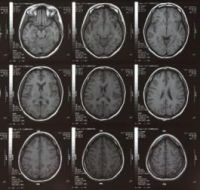

Amikor erotikus képeket mutattak nekik, a pedofilek hypothalamusában (többek között az ébrenlétért és hormonfelszabadulásért felelős agyi központ) kisebb volt az aktivitás, mint egészséges emberek esetén.

A tanulmány, mely a Biological Psychiatry című lapban jelent meg, elsőként támasztja alá bizonyítékokkal, miben tér el a pedofilok agyműködése a normálistól. „Megfigyelésünk az első lépés a pedofília neurobiológiájának feltérképezése felé, amely hozzájárulhat új és hatékony gyógymódok kifejlesztéséhez.” – mondta Dr. Georg Northoff, a kutatás vezetője.

„Nem tudni, hogy a kutatásban említett eltérő agyi aktivitási mintázatok alapján megjósolható-e, hogy kiből lesz pedofil" – írta Dr. John Krystal szerkesztői kommentárjában. „Az eredmények azonban segítenek megérteni a rendellenesség összetettségét. Az agyi aktivitás eltérései tehetik hajlamossá a pedofil egyént arra, hogy a stimulációk más formáit keresse.” – tette hozzá Dr. Krystal.